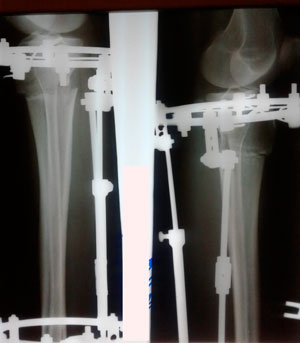

Дата операции - 24.10.2019г.

Дата снятия аппаратов - 22.01.2020

Срок сращения - 89 дней.